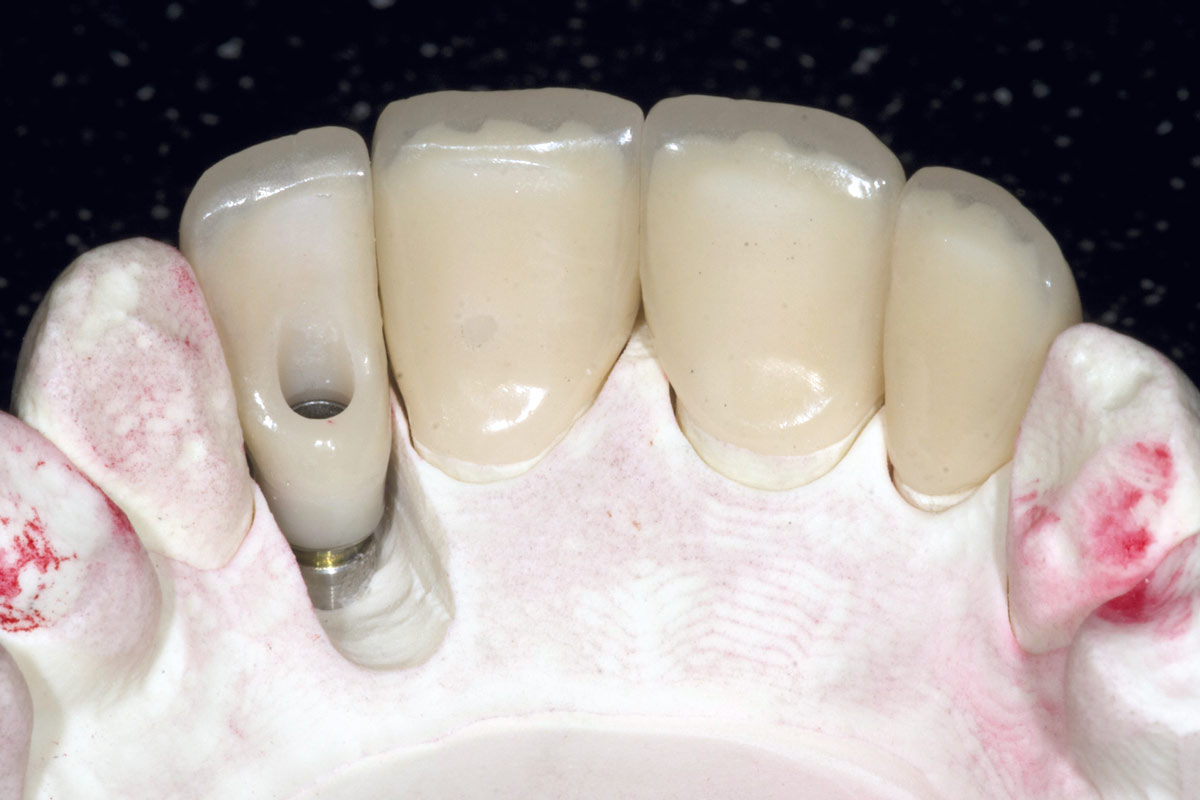

15/19 - Screw retained final implant prosthesis and adjacent ceramic unitsBone augementation with maxresorb® - Dr. R. Cutts